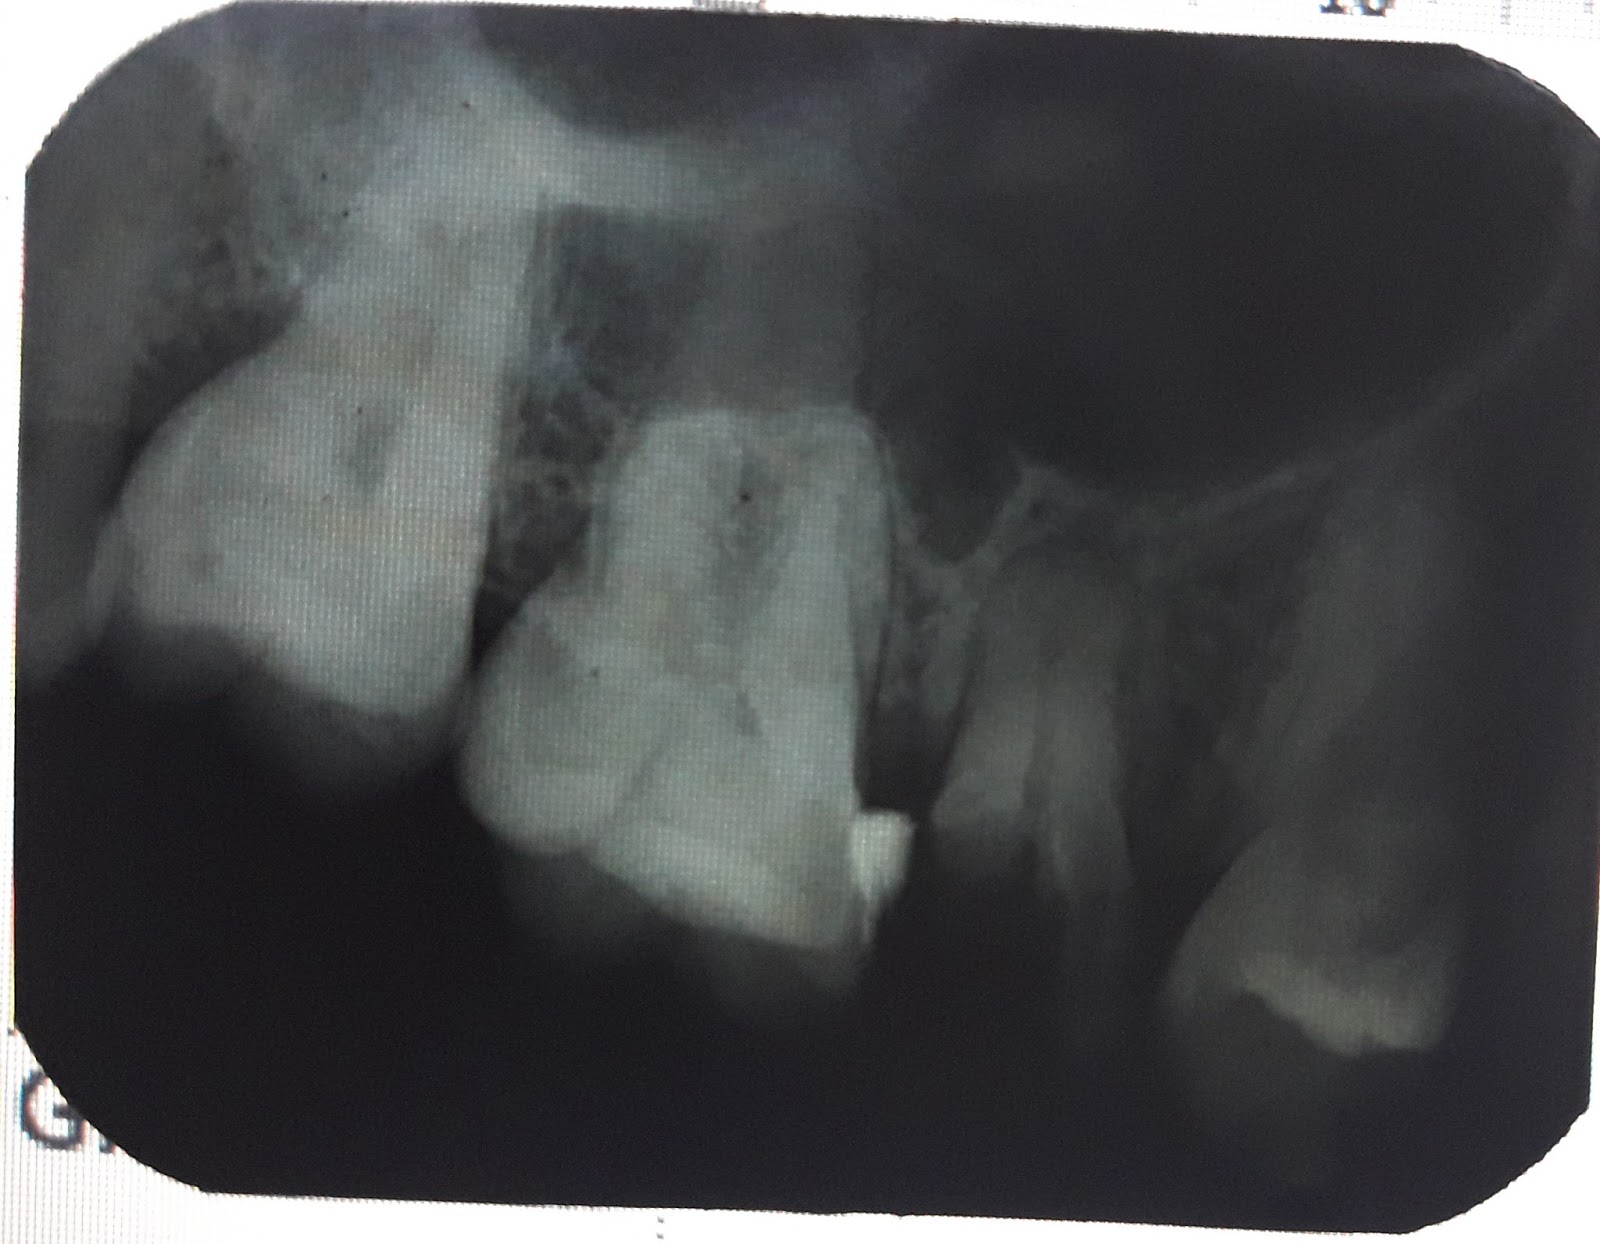

Akar gigi geraham mati. Sebelum ni aku sendiri tak pernah tahu tentang ada nya rawatan akar gigi ni. Perawatan saluran akar pengobatan ini biasanya direkomedasikan terlebih dahulu bila penyebab gigi mati tidak terlalu parah dan gigi masih dalam keadaan baik. Ini adalah prosedur standar untuk memasang kembali gigi yang retak setelah ekstraksi dan harus mengidentifikasi struktur gigi yang hilang. Selamat siang dok saya putri berumur 22 tahun 7 tahun yang lalu saya mencabut gigi geraham pertama saya sebelah kanan.

Perawatan saluran akar gigi diperlukan apabila pembusukan sudah mencapai bagian dalam gigi pulpa atau saraf yang sudah mati. Gigi yang telah mati non vital gigi yang mempunyai tampalan besar dan diindikasikan untuk pembuatan korona kadang kadang perlu rawatan kanal akar dilakukan terlebih dahulu untuk peletakan tiang dan teras. Pertama gigi tersebut biasanya mengalami kerusakan atau lubang yang sangat besar dan dalam. Bahaya akar gigi yang tertinggal.

Joy runut tanda tanda dari awal prosesnya ya. Ada kemungkinan bahwa sepotong akar gigi yang retak bisa jatuh kembali ke dalam gusi. Rawatan endodontik salur akar gigi adalah alternatif bagi gigi yang rosak teruk berikutan tisu pulpa dijangkiti atau mati supaya gigi tidak perlu dicabut dan boleh terus kekal berfungsi. Perawatan ini dilakukan dengan membuang jaringan saraf jaringan pembuluh darah dan setiap daerah yang busuk pada setelah bersih dokter gigi dapat melakukan tambalan atau memberikan crown sehingga gigi tidak perlu.